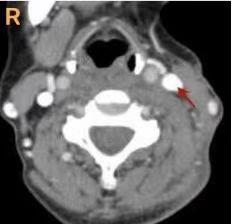

患者,女性,55岁。因“被犬咬伤左侧颈部致疼痛出血4 h”于2023-02-19 21:40送入本院抢救室,家属诉患者4 h前被犬咬伤颈部及左下肢,伤口疼痛伴大量出血,量约500 mL, 有头晕目眩,胸闷恶心,无呕吐。查体:体温36.4 ℃,呼吸频率20次/min,脉率72次/min,血压88/51 mmHg(1 mmHg=0.133 kPa),SaO2 95%。神志清,精神差,面色苍白,眼部及面部皮肤挫伤,左侧颈部4处伤口,最大处5 cm,余为2 cm、2 cm、1 cm(图 1),左小腿内侧12 cm皮肤撕裂伤,外侧4 cm、8 cm两处撕裂伤,均有活动性出血,肢体活动尚可。入院后予创口加压包扎止血。颈部增强CT示:左侧颈内静脉损伤(图 2)。诊断:(1)颈部开放性损伤;(2)失血性休克;(3)下肢开放性伤口。予以输注“去白红细胞2 U及冰冻血浆200 mL”,注射狂犬病免疫球蛋白等处置后建议急诊手术探查,家属知情同意后入手术室行颈部探查术+清创缝合术。术中见左颈4处伤口,最大处5 cm,余2 cm、2 cm、1 cm,延长大切口至7 cm左右予以探查,见左侧胸锁乳突肌部分断裂,分开肌肉见左颈内静脉局部裂口,边缘毛糙,长度约1 cm,裂口内血栓形成,取出血栓后见鲜血涌出,予血管破口缝合止血(图 3)。探查其余3处切口,左下切口较深,予以延长切口至3.5 cm左右,未见明显血管损伤,碘伏及生理盐水交替冲洗各伤口,两处较长伤口各放置引流片1条,颈部无菌敷料加压包扎伤口,左小腿创口清创缝合,全麻清醒后回耳鼻咽喉科病房。

| 图 2 术前颈部增强CT示左侧颈内静脉损伤 |